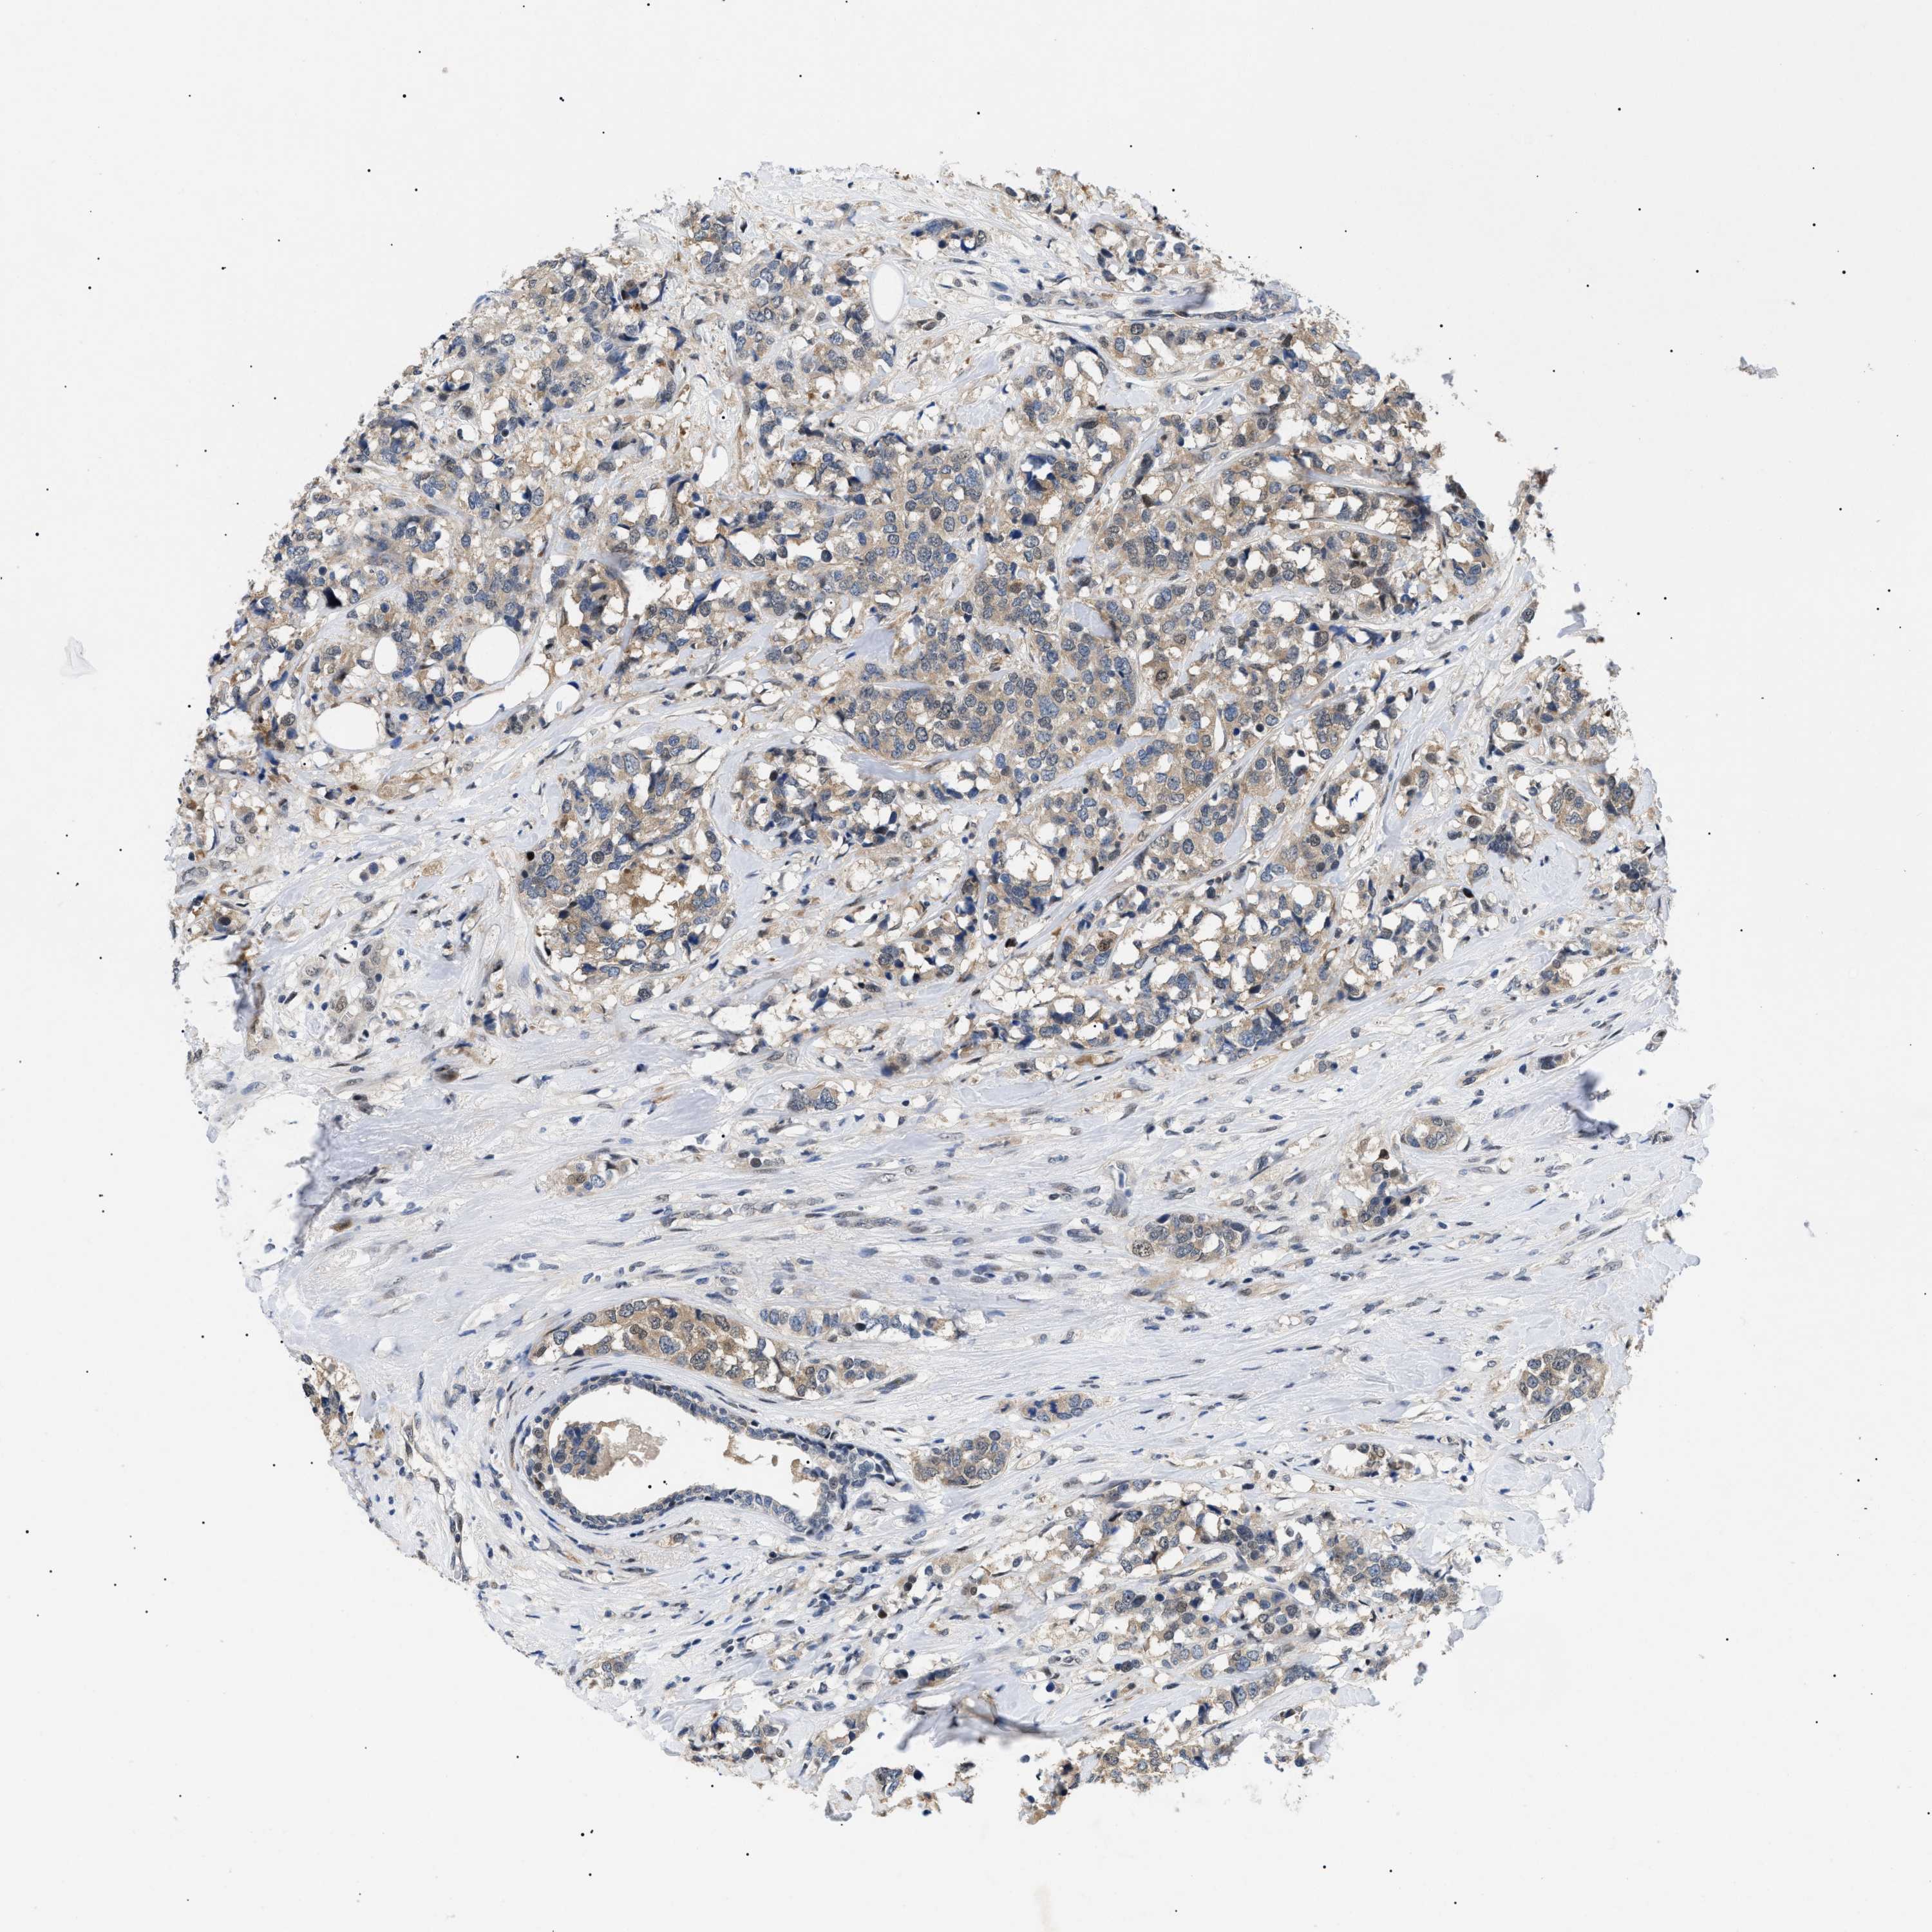

BRCA TCGA BRCA VALIDATION PROTEIN EXPRESSION